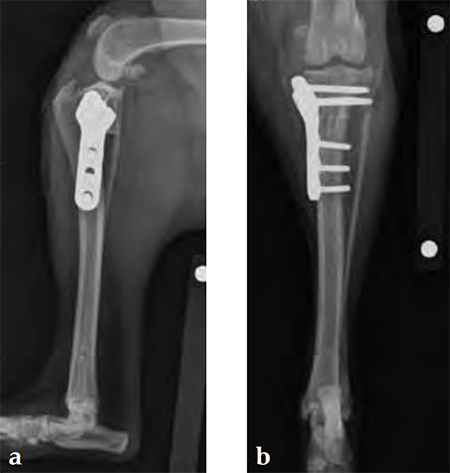

An 8-year-old, female, spayed, 24 kg Australian cattle dog. This breed has short stocky legs and is very energetic and strong. The added strength of the 3.5 mm plate over the TPLO 2.7 mm plate was an advantage. The smaller head profile and shorter length of the TPLO 3.5 mm small stature plate allowed it to fit nicely on this patient.